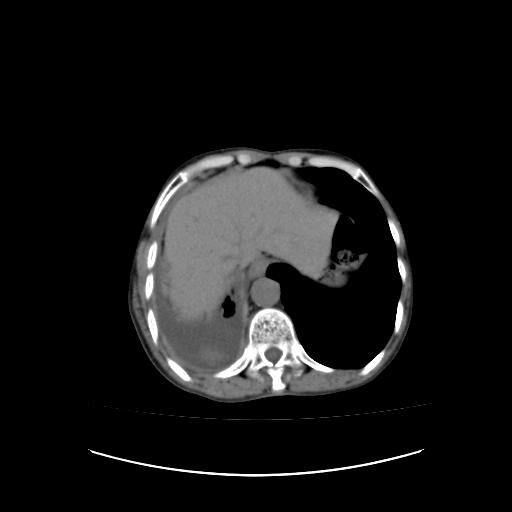

右侧胸廓塌陷,右侧胸膜广泛增厚并见多发胸膜结节,右侧少量胸腔积液并包裹。

恶性胸膜间皮瘤伴肺内转移可能性大;或胸膜、肺内均为转移瘤,左肺下叶亦见多发小结节影。

右胸腔结节均考虑来自胸膜(部分来源于叶裂),考虑胸膜间皮瘤或转移瘤.